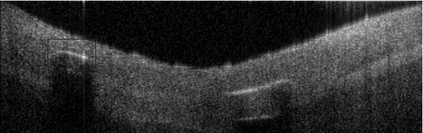

Coronary artery disease (CAD) is a cardiovascular condition with high morbidity and mortality. Intravascular optical coherence tomography (IVOCT) has been considered as an optimal imagining system for the diagnosis and treatment of CAD. Constrained by Nyquist theorem, dense sampling in IVOCT attains high resolving power to delineate cellular structures/ features. There is a trade-off between high spatial resolution and fast scanning rate for coronary imaging. In this paper, we propose a viable spectral-spatial acquisition method that down-scales the sampling process in both spectral and spatial domain while maintaining high quality in image reconstruction. The down-scaling schedule boosts data acquisition speed without any hardware modifications. Additionally, we propose a unified multi-scale reconstruction framework, namely Multiscale- Spectral-Spatial-Magnification Network (MSSMN), to resolve highly down-scaled (compressed) OCT images with flexible magnification factors. We incorporate the proposed methods into Spectral Domain OCT (SD-OCT) imaging of human coronary samples with clinical features such as stent and calcified lesions. Our experimental results demonstrate that spectral-spatial downscaled data can be better reconstructed than data that is downscaled solely in either spectral or spatial domain. Moreover, we observe better reconstruction performance using MSSMN than using existing reconstruction methods. Our acquisition method and multi-scale reconstruction framework, in combination, may allow faster SD-OCT inspection with high resolution during coronary intervention.